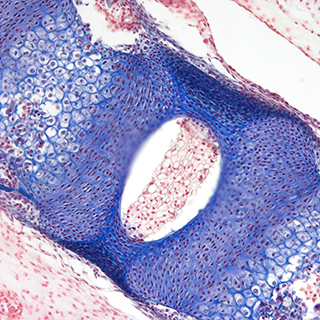

Dhyana 400DC(簡(jiǎn)稱(chēng):400DC)是一款前照式彩色sCMOS 相機(jī)。它兼具科研級(jí)靈敏度和真實(shí)色彩還原能力,具有寬闊的視野和卓越的動(dòng)態(tài)范圍,即使在弱光下也能拍攝高質(zhì)量彩色圖像。

采用高靈敏彩色sCMOS圖像芯片,兼具科研級(jí)的靈敏度和真實(shí)色彩還原能力,無(wú)論明場(chǎng)還是暗場(chǎng)拍攝,都能清晰拍攝細(xì)節(jié)豐富的彩色圖像。